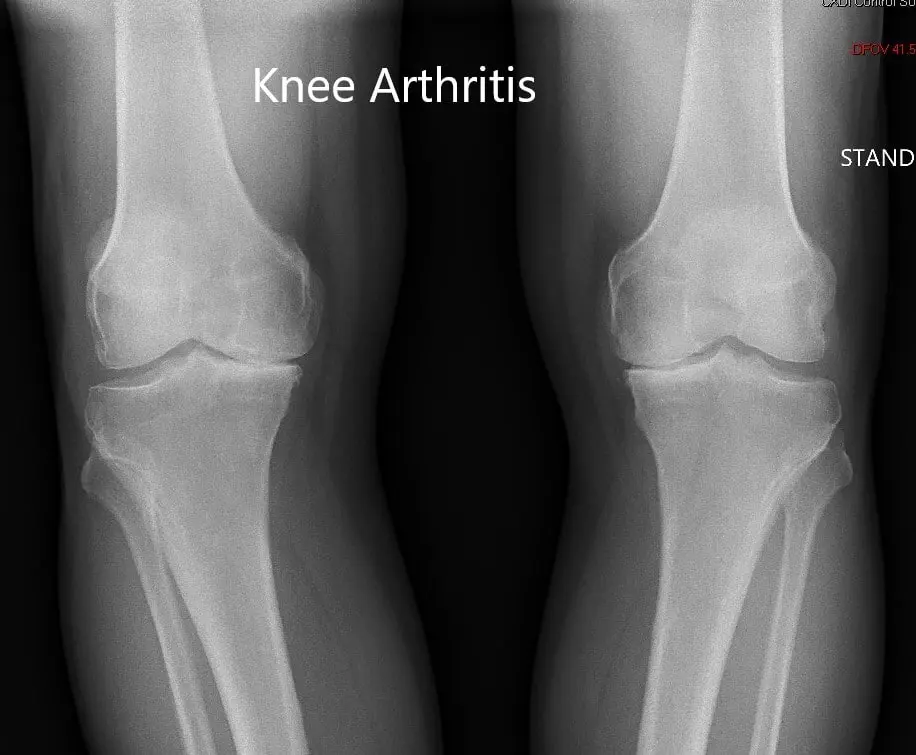

Preoperative X-ray showing the AP view of both the knee joints